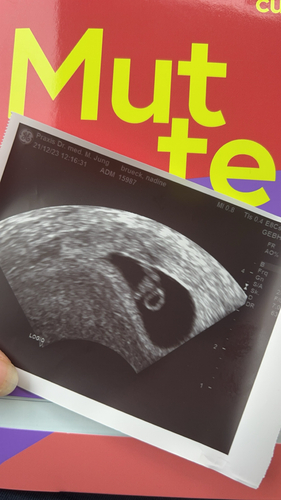

Endlich ein Herzschlag & 2 stolze CM groß bei 8+4